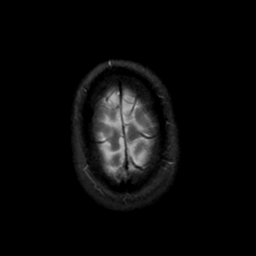

MR Study #18, July 21, 1991 -- Slice #46

[Home][Help][Clinical][Tour 1][Tour 2] Slice 46